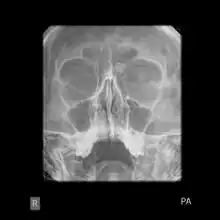

Medical imaging such as X-ray, CT scan and MRI show dense, clearly defined, round white tumors attached to bone.[1] They can be left alone if not troubling, and surgically cut out if pressure symptoms.[1] The surgery may be possible through the nose, without making a large cut.[3]

Medical imaging such as X-ray, CT scan and MRI show dense, clearly defined, round white tumors attached to bone.[1] They may be diagnosed when having medical imaging for another reason.[3] Osteomas of the paranasal sinuses and skull base can be diagnosed using CT-scan without intravenous contrast, allowing its size and relation to nearby important structures to be assessed.[3] A biopsy is not usually required.[3]